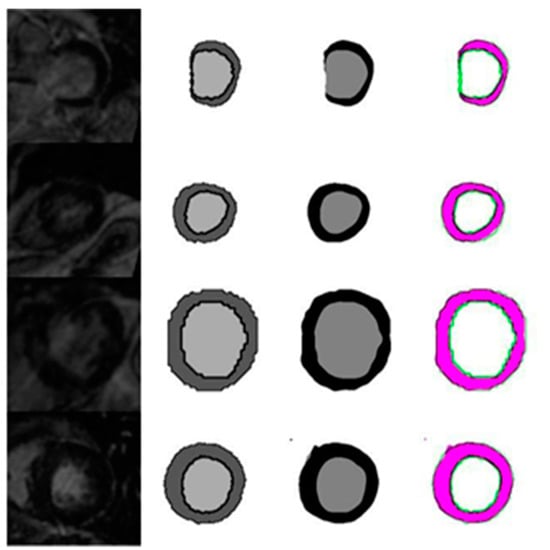

4.1. Evaluation of the Effects of Image Size on the Quality of Automatic Segmentation with U-Net against the GT Segmentation

4.1.6. Evaluation of Automated Segmentation with U-Net and GT Segmentation Using LGE MRI Test Images